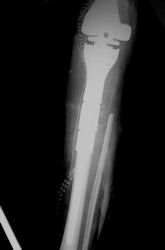

Examples of radical limb sparing surgeries for osteosarcomas in various anatomic locations (distal femur, proximal tibia, proximal humerus, scapula)

In each case, the tumor and bone from which it arose were resected. This required meticulous dissection, mobilization and preservation of adjacent pertinent neurovascular structures. In each case presented here, the defect was reconstructed with a special modular segmental tumor prosthesis. This also replaces the adjacent joint in many instances.

| Proximal Tibia Osteosarcoma: Limb-Sparing Surgery |

Postoperative X-Rays